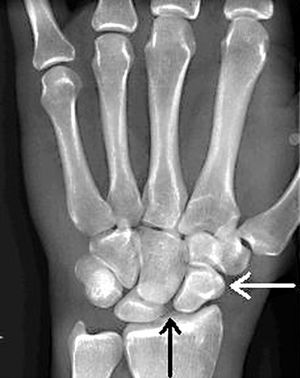

Black arrow: Scapholunate joint space widening; White arrow: Cortical ring sign

• Widening of the scapholunate joint space >3mm

• Know as Terry-Thomas sign (or David Letterman sign)

• PA view: Cortical ring sign (circular cortex of the bone is more prominent)